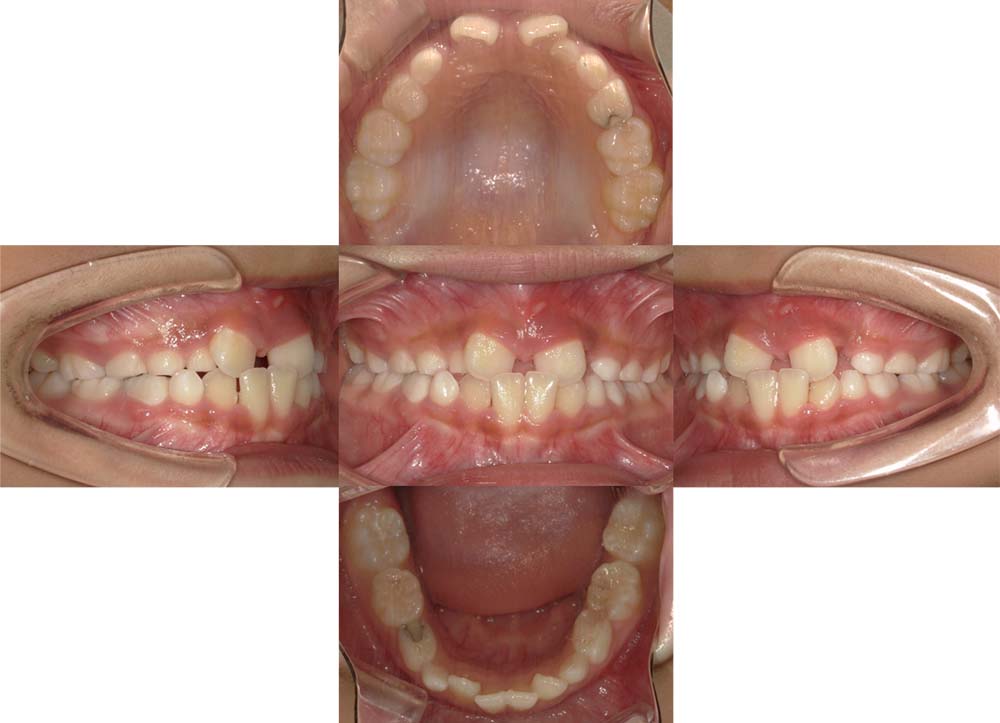

症例10

| 主訴 | 前歯が反対に噛んでいる |

| 診断名あるいは主な症状 | 反対咬合 |

| 年齢/性別 | 9歳・男児 |

| 矯正ステージ | 子どもの矯正治療 |

| 治療方法 | リンガルアーチ |

| 抜歯部位/抜歯有無 | – |

| 治療内容 | リンガルアーチにて反対咬合を改善。その後は成長と生え変わりの定期的なチェックを行った。 |

| 費用 | 30万円程度(2025.5での料金となります。) |

| 治療期間 | 1年0ヶ月程度 |

| 主なリスク・副作用 | 痛み、歯根吸収、歯肉退縮、虫歯、後戻り |